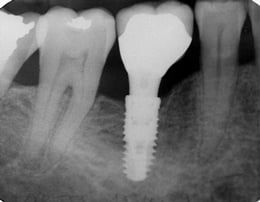

Un implante dental se divide principalmente en 3 partes las cuales son:

El implante (Elaborado principalmente de titanio)

El pilar (Pieza que une el implante con la corona o prótesis)

La corona o prótesis (Parte visible, lo que da el aspecto de diente natural)

Las 3 partes forman un implante dental completo, a la derecha se aprecia el implante, una imagen dice más que mil palabras.